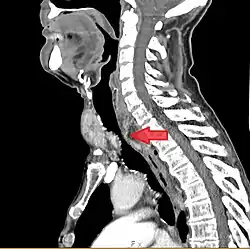

![]() Podgłośniowe zwężenie pointubacyjne na zdjęciu rentgenowskim |

Badania obrazowe

W obrazowaniu krtani stosuje się tomografię komputerową, czasem także rezonans magnetyczny. W przypadkach wrodzonego porażenia fałdów głosowych konieczne jest wykonanie rezonansu magnetycznego głowy w celu wykluczenia wad ośrodkowego układu nerwowego. Zdjęcia rentgenowskie, ze względu na nakładające się cienie tkanek miękkich i kości, mają mniejszą wartość diagnostyczną[108][23].

Spiralna wielorzędowa tomografia komputerowa z rekonstrukcją 3D umożliwia ocenę długości zwężenia i stanu dróg oddechowych poniżej niego, nawet w zwężeniach krytycznych, identyfikację ewentualnych uszkodzeń chrząstek i mnogich zwężeń, a także ocenę stanu struktur otaczających. Ograniczenia tomografii to brak możliwości oceny stanu błony śluzowej i ruchomości struktur krtani oraz niemożliwość podejmowania działań leczniczych[5][109].